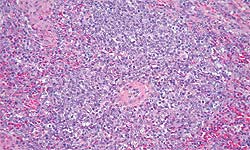

Rate d'un porc atteint de MAP correspondant à un cas diagnostiqué en 1996 au Canada.

Déplétion lymphocytaire modérée et infiltration histiocytaire du tissu lymphoïde. Coloration HE (hématoxilline-éosine). (Photo cédée par le Dr. Edward G. Clark, Prairie Diagnostic Services, Canada) |